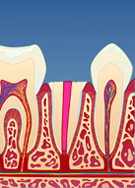

Av og til knekker en tann i nivå med tannkjøttet. Dersom tannen er rotfylt, er det likevel mulig å bygge den opp igjen. Siden det er lite tannsubstans igjen (fig. I), må det først monteres en stift i den rotfylte tannen. Stiftens funksjon er å forankre oppbygningen.

figur I